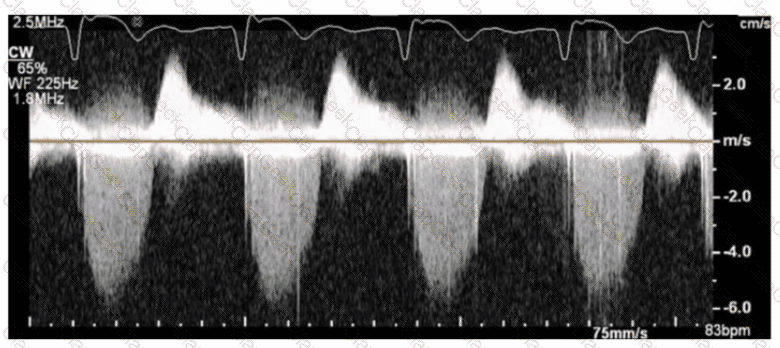

The sonographer obtains this Doppler signal while using the non-imaging transducer in the apical position. What is the best way to differentiate between mitral regurgitation and aortic stenosis signals in the waveform shown in this image?

Which patient positioning is best for obtaining the waveform seen in this image obtained by a non-imaging transducer?